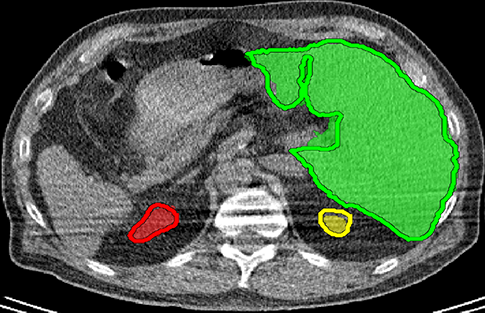

We applied our method on PET-CT scans of three different subjects to segment their liver, left kidney, right kidney and the background. Although we applied our method and Potts model on the 3D volumes we only show the results on a few representative slices from each volume in Fig.11. Also, the results of different methods for each subject were computed using the same smoothness. We can see from the last two rows which compare our method to Potts, using Hedgehogs constraints enabled us to avoid geometrically incorrect segmentations, e.g. one liver inside the other (last-row middle), or parts of left kidney is between the right kidney and liver (last-row right). Furthermore, for test subjects 1 and 2 the kidneys and background were poorly segmented by Potts model, e.g. most of the kidneys were segmented as background for test subject 1. Potts poor performance is due to the large overlap between the kidneys and background color models. This overlap resulted in an in-discriminative data term for Potts to properly separate them. This issue becomes worse in iterative frameworks where color models are re-estimated based on current segmentation. To be specific, if at any iteration Potts model resulted in a bad segmentation then re-estimating the color models will bias them towards the bad segmentation and subsequent iterations worsen the results. Comparing our results for subjects 1 and 2 to Potts model shows that our method is less prone to the aforementioned issue as we forbid undesirable segmentations, i.e. those that do not respect shape constraints.

| Subject 1 | Subject 2 | Subject 3 | |||

| Our method (Hedgehogs Shapes + Potts) | ![]() |

![]() |

||

|||

| \rdelim}1910pt Same Slice | |||||

|

Potts |

For quantitative comparison, Table 1 lists for each organ of a subject the Score, Precession and Recall measures of our method and Potts model where For the kidneys, our method clearly out performed Potts model, e.g. note Potts model poor precision/recall for subjects 1 and 2. For the liver, both methods performed comparably.